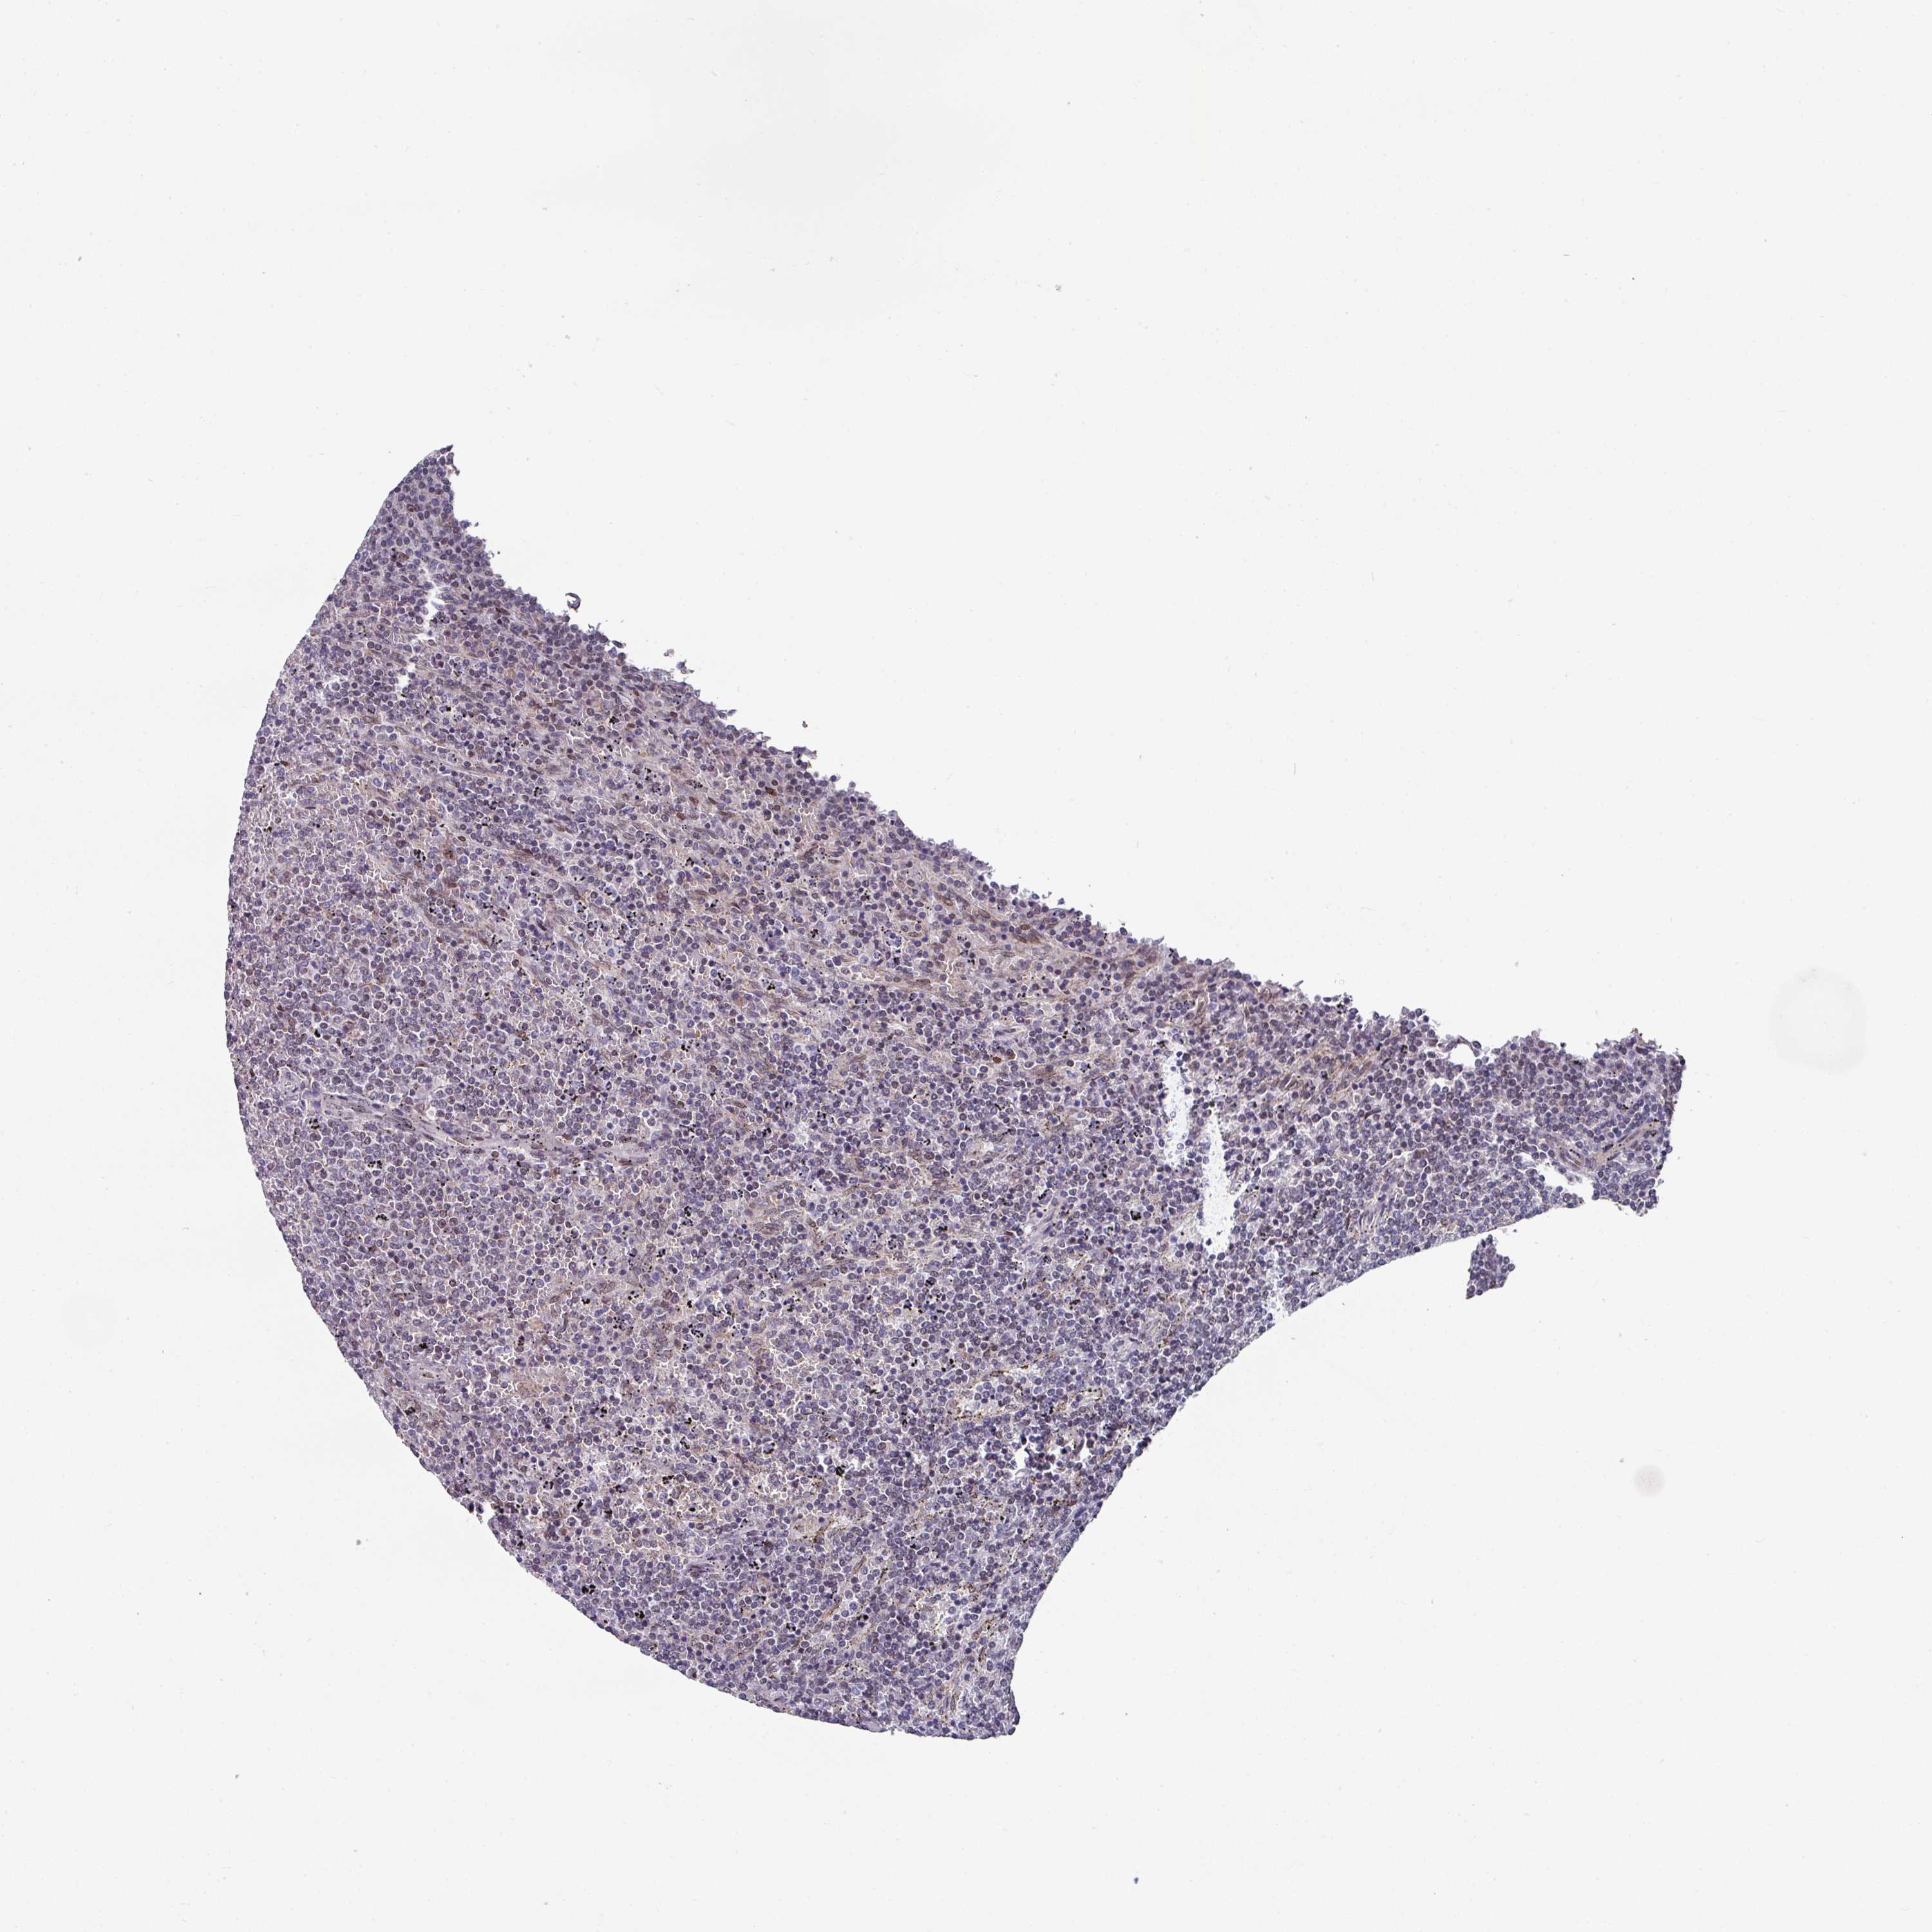

LYMPHOMA - Protein expressioni

A mouse-over function shows sample information and annotation data. Click on an image to view it in a full screen mode. Samples can be filtered based on level of antibody staining by selecting one or several of the following categories: high, medium, low and not detected. The assay and annotation is described here.

Each image is clickable and will lead to virtual microscopy that enables deeper exploration of all samples and also displays staining intensity scores, fraction scores and subcellular localization as well as patient and tissue information for each sample.

Staining

High

Medium

Low

Not detected

Intensity

Strong

Moderate

Weak

Negative

Quantity

>75%

75%-25%

<25%

None

Location

Nuclear

Cytoplasmic/membranous

Cytoplasmic/membranous,nuclear

Hodgkin's disease, NOS

Malignant lymphoma, non-Hodgkin's type, High grade

Malignant lymphoma, non-Hodgkin's type, Low grade